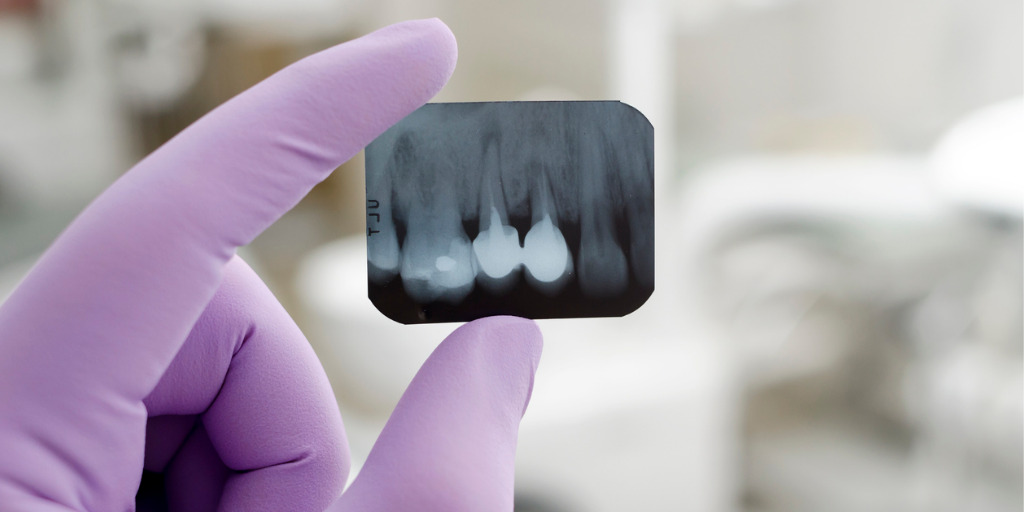

- Wurzelbehandlung – Ablauf: Der Zahnarzt erstellt zuerst ein Röntgenbild. Dann eröffnet er den Zahn, um Zugang zum Wurzelkanal zu erhalten. Er entfernt das kranke Gewebe, spült die Zahnwurzeln mit einer desinfizierenden Lösung durch, legt ein Medikament ein und verschließt den Zahn provisorisch bis zum nächsten Termin. Dieser Vorgang wird wiederholt, bis der Zahn bakterien- und entzündungsfrei ist. Dann erfolgt die definitive Wurzelfüllung. Muss der Zahnarzt die Wurzeln entfernen, heißt das Wurzelspitzenresektion.

Wer Karies vorbeugen möchte, hält sich an die zahnärztlichen Empfehlungen für die häusliche Zahnpflege und nimmt regelmäßig Zahnarzt-Kontrolltermine wahr. Denn zuverlässig und möglichst frühzeitig Karies oder Karies-Ursachen erkennen und beseitigen … das kann nur der Profi. Vor allem wenn es sich um Zahnzwischenraum-Karies oder auch Karies unter einer Krone handelt, bringt oft erst ein Röntgenbild Gewissheit über die Karies-Erkrankung.